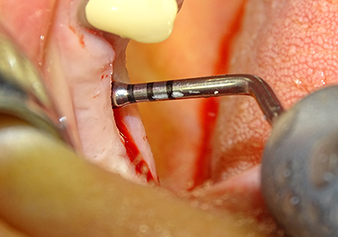

Dopo la preparazione atraumatica del lembo mucoperiosteo, con l'ausilio dello strumento I1 è stata contrassegnata la posizione e preparata la sede dell'impianto fino ad avvertire la resistenza iniziale. Gli strumenti piezochirurgici sono stati utilizzati eseguendo un movimento verticale ascendente e discendente senza dover esercitare alcuna pressione. La vibrazione piezoelettrica ha generato la cavitazione richiesta ad elevata efficienza.

Lo strumento I2A (diametro 2,0 mm) è stato quindi impiegato per perforare il pavimento sinusale in modo graduale e su superfici molto ridotte. Tale metodo piezochirurgico previene il danneggiamento della membrana di Schneider. Durante l'utilizzo di Z25P, la membrana risultava già essere leggermente sollevata dal fluido di raffreddamento fornito attraverso la punta dello strumento (Fig. 3). La quantità di fluido di raffreddamento presente era solo del 50% per evitare che la sede dell'impianto registrasse un'elevata pressione.